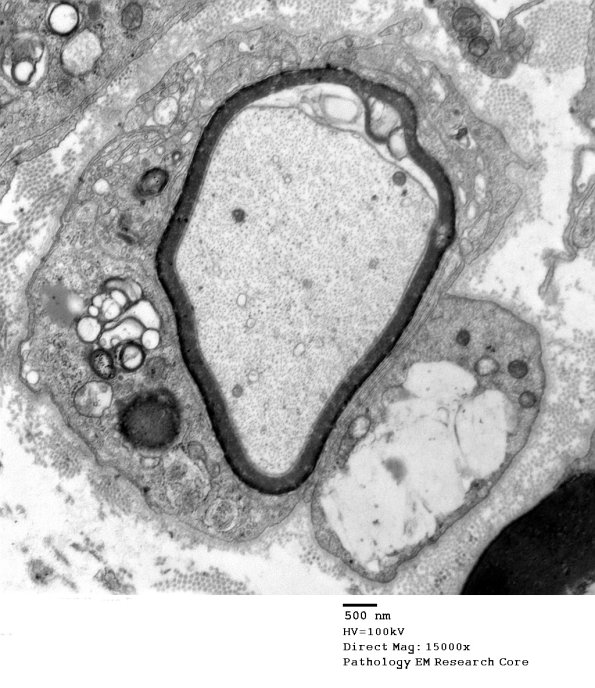

Washington University Experience | PERIPHERAL NEUROPATHY | 7A GUILLAIN-BARRE SYNDROME (GBS) | 3B3B Case 3 GBS Nerve Bx_010 - Copy

I think this is remyelination after completion of demyelination but some calls are iffy. (electron micrographs)